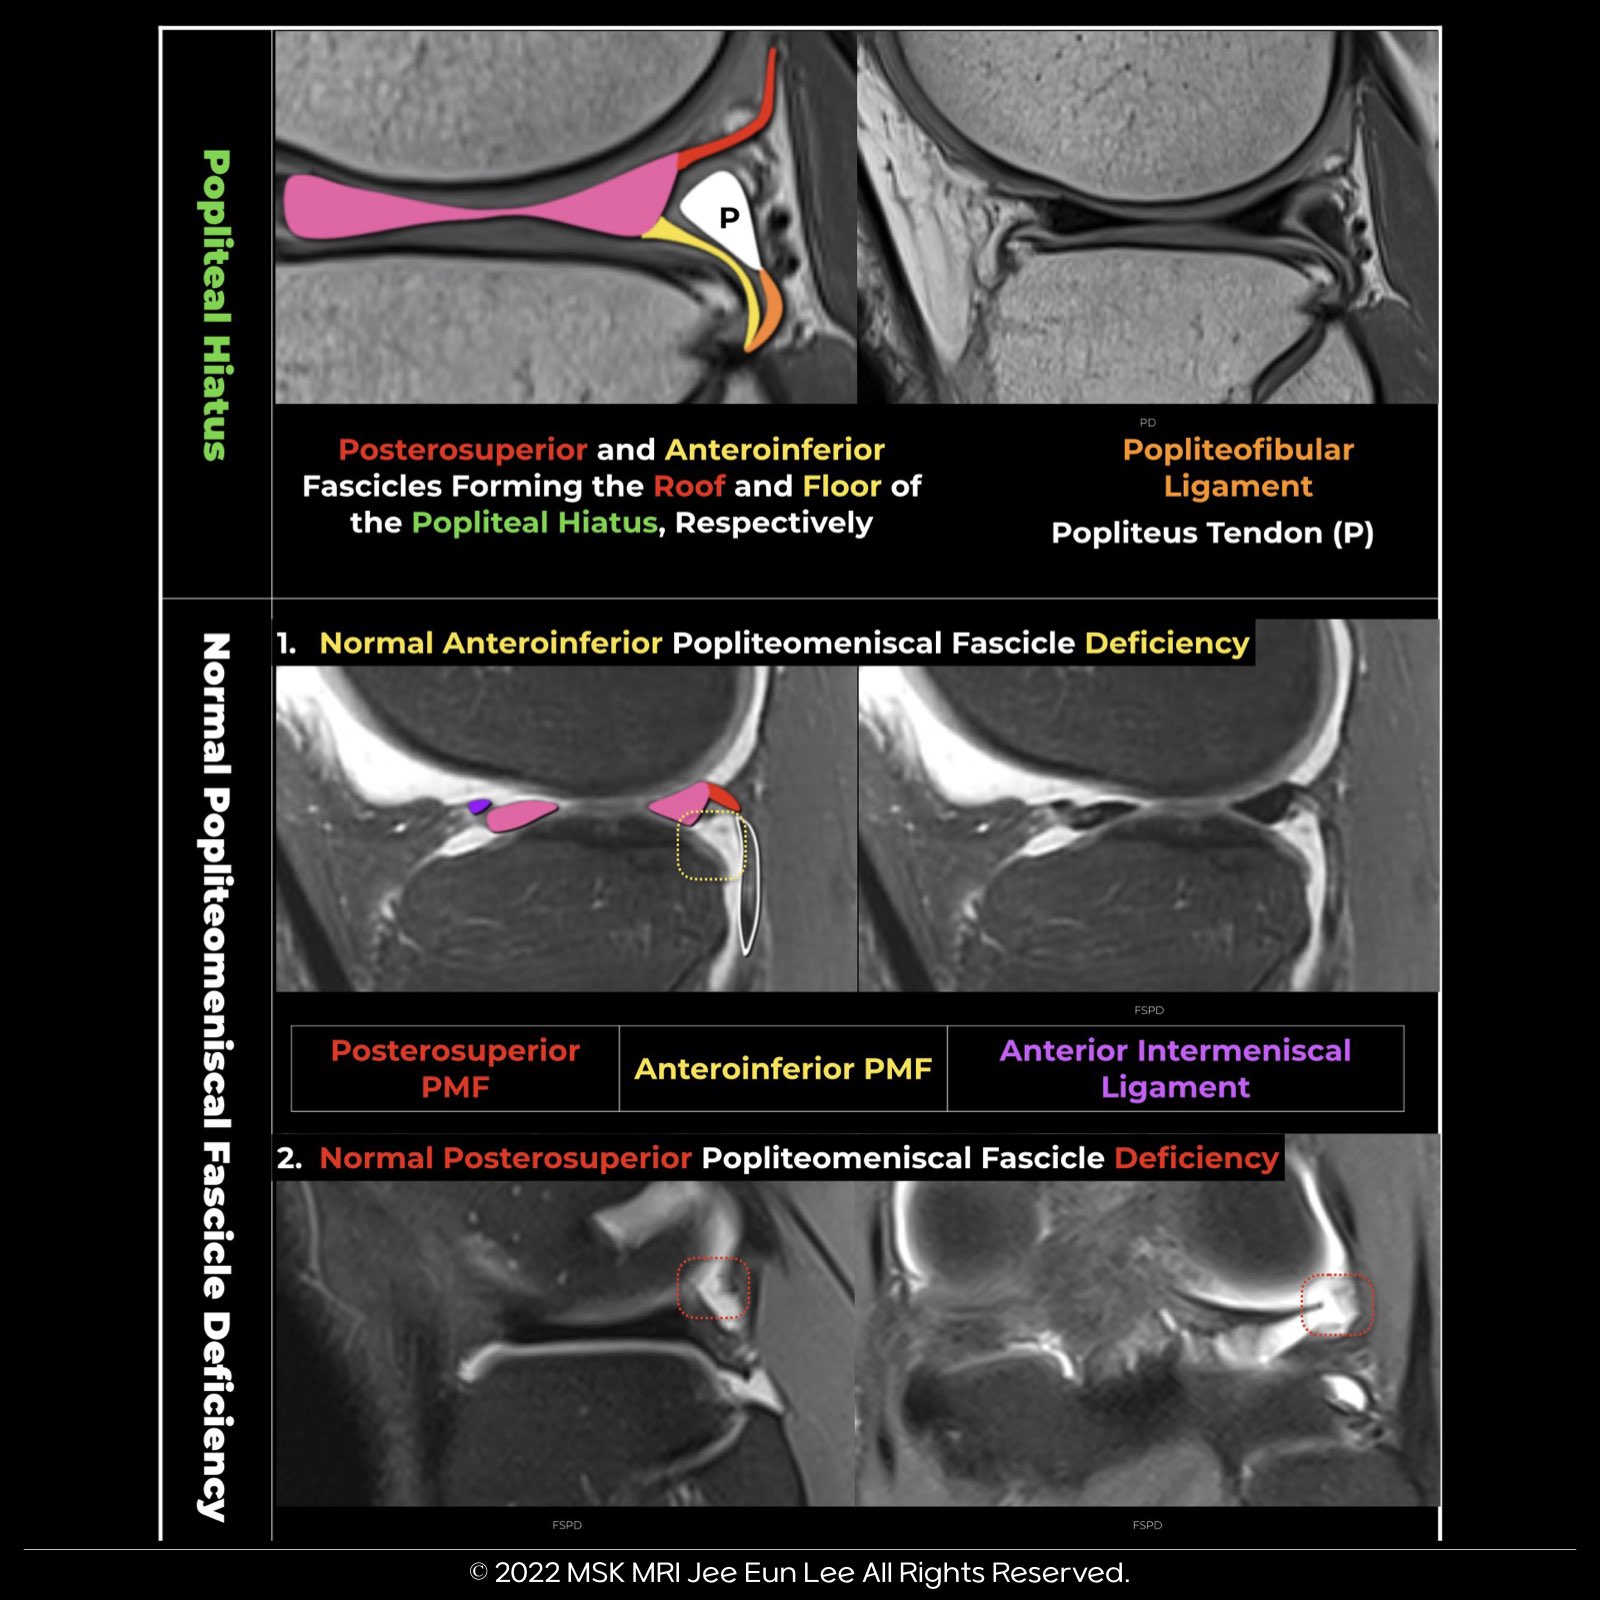

👉Anteroinferior Popliteomeniscal Fascicle: This fascicle forms the lateral floor of the popliteal hiatus, varying in thickness. It connects the lateral meniscus’s body, extends to the popliteus muscle’s musculotendinous unit, and blends with the popliteofibular ligament, inserting at the fibular head’s styloid process.

👉 Posterosuperior Popliteomeniscal Fascicle: Linking the upper margin of the posterior horn of the lateral meniscus to the popliteus tendon and the posterior joint capsule, it forms the roof of the popliteal hiatus.

💡 Interesting Fact: For the popliteus tendon to move from inside the joint to outside, specifically from the lateral to the medial side of the hiatus, there are normally two deficiencies in the Popliteomeniscal Fascicle (PMF), both above and below.

- Normal Anteroinferior Popliteomeniscal Fascicle Deficiency

- Normal Posterosuperior Popliteomeniscal Fascicle Deficiency